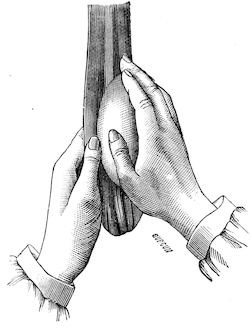

Fig. 1.—Rachitis in a young goat.

Rachitis is a disease of youth, and is common both to the human species and to all domestic animals. It is characterised by irregularities in development and by imperfect consolidation of the bones. The boundary between rachitis and osseous cachexia is difficult to define and in fact at the present moment the two diseases can scarcely be defined with exactitude. Rachitis again is often complicated with softening of the bones, disease of the limbs, arrested development, etc., but it must not be forgotten that although the irregularities in ossification and development of the skeleton are the symptoms most striking to the eye, they do not stand alone, and that from the point of view of development all the tissues, including the muscles, are more or less affected and that most of the physiological functions such as digestion and the secretion of urine are deranged.

Symptoms. The onset is absolutely insidious and the diagnosis of rachitis is never made until nutrition has long been abnormal.

This disturbance of nutrition is revealed by irregularity and abnormality in appetite, by difficulty in rising and moving about, and by the animals lying down for long periods. The subjects are feeble, sluggish and badly developed.

Next supervenes the second phase characterised by deformity of bones. This is of two kinds—deformity in the neighbourhood of joints (deformity or enlargement of the epiphyses) and deformity of the diaphyses. The former results from irregularity in ossification of the articular cartilages. The latter is followed by loss of rigidity in the bones of the limbs which, under the influence of the body weight and of muscular contraction, bend in different directions.

The bones appear of increased thickness principally towards the 6articulations. The latter are deformed, and on palpation are found to be surrounded by uneven and irregular growths.

The front limbs are distorted. In young pigs, lambs, and less frequently in foals, calves and dogs, the jaws become deformed, and mastication is rendered difficult.

The vertebral column may also be affected, and lordosis (bending downwards of the back) or skoliosis (lateral bending of the back) is somewhat frequent.

Cyphosis, or upward bending of the back, seldom occurs, and when seen, sometimes results from disease other than rachitis.

General development is always interfered with and the young creatures are generally dwarfed.

The digestive apparatus is disordered, the appetite is irregular and sometimes depraved, while indigestion, gastritis, and enteritis are not exceptional. Physiological and pathological research has shown that the quantity of phosphoric acid eliminated in twenty-four hours in a rachitic child is double the quantity passed by a healthy infant. The amount of urea in the urine (which is a criterion of nutrition, and usually varies in proportion to the amount of food ingested) is, on the contrary, diminished even when highly nitrogenous food is given, thus suggesting diminution in nutrition.

Lesions. The lesions are represented by abnormal and irregular thickening around the interarticular cartilages. The cartilage is thickened, compressible, very spongy and without regular ossification. Diffused periostitis exists principally towards the extremities of the bone. Beneath the periosteum the surface of the bone appears rough and softened. On section the medullary canals are seen to be enlarged and filled with marrow of a gelatinous character. The Haversian canals are dilated, and the entire tissue appears very vascular. Chemical analysis proves that the mineral constituents of the bone, particularly the phosphates, have diminished by one-half; the organic constituents on the other hand are increased in a similar ratio, but the ossein is abnormal. Ossification has, in a word, been incomplete.

7Diagnosis. Diagnosis presents no difficulty except in the early stages before deformity has occurred.

Rachitis can scarcely be mistaken for any other condition except perhaps infectious rheumatism, but the rapid course of the disease in the latter case, the persistence of fever and the swelling of the joint cavities sufficiently differentiate the conditions provided care is exercised.

Prognosis. From an economic point of view the prognosis is very grave for if the lesions are extensive there is nothing to be gained by keeping the animal.

Treatment. Treatment differs very little, whether the animals are still being suckled or have been weaned. In the former case it is necessary to improve the quality and chemical constitution of the mother’s milk by giving food, richer both in mineral salts and in nitrogenous material.

Cooked grains, milk, and forage of good quality should be given freely. When the mothers are exhausted and anæmic it is better to feed the little animals artificially or to change them to a foster-mother. Those already weaned should be given good rich milk, eggs, boiled gruel, and drugs, such as the phospho-chlorate of lime, 1 to 1½ drachms per day (for a calf); lacto-phosphate of lime, 1 to 1½ drachms; bi-phosphate of lime, 1 drachm, or simply ordinary phosphate of lime. Oil containing 1 per cent. of dissolved phosphorus may be given in doses of 1 to 2½ drachms, according to the size of the calves, but its use calls for much care, and it should only be given for alternate periods of a fortnight. The glycerophosphates are not very active. Beef meal in doses of 6 drachms to 1½ ounces and chloride of ammonium in doses of 30 to 60 grains have also been used advantageously. The above drugs, but particularly the bi-phosphate of lime and chloride of ammonium, stimulate nutrition and diminish the quantity of phosphoric acid eliminated.